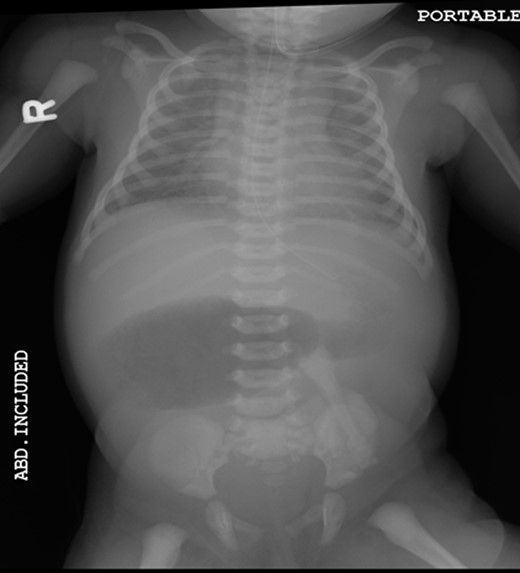

A 1-day-old baby girl, born by normal spontaneous vaginal delivery, was evaluated for abdominal distension and history of having not passed meconium. An abdominal X-ray was suspicious for malrotation (Fig. 1). The patient did not have any evidence of sepsis. An echocardiogram ruled out any congenital cardiac anomalies.

Pre-operative abdominal x-ray showing a gastric and duodenum distention with paucity of small bowel gas distally, suggesting duodenal atresia and malrotation.